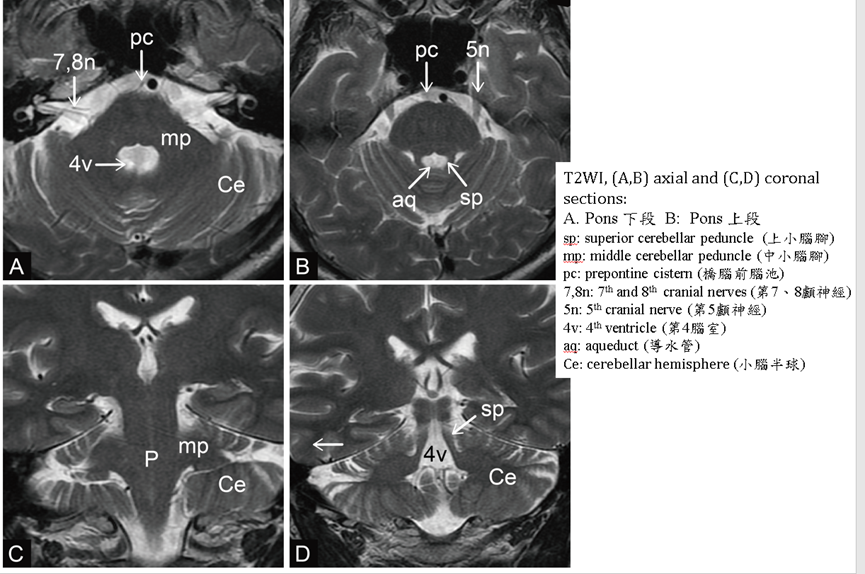

在CT、MRI橫切面,pons看起來像蘋果形狀